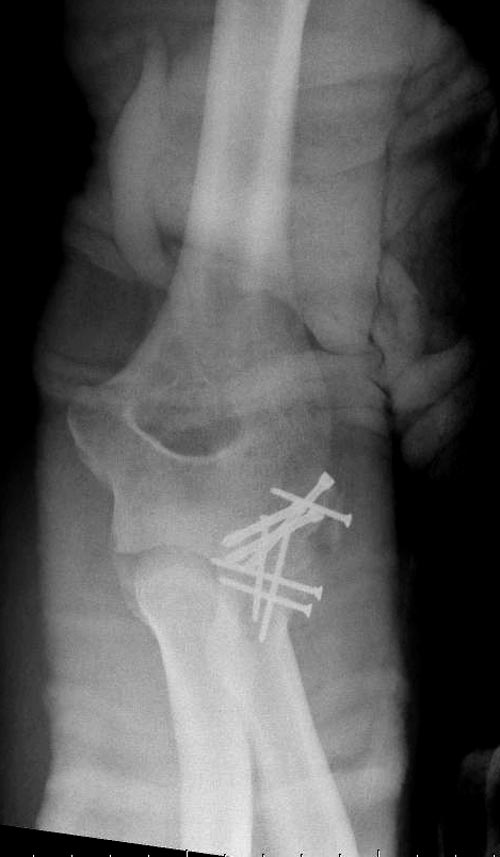

Re: ПЕРЕЛОМ ГОЛОВКИ ЛУЧЕВОЙ КОСТИ.